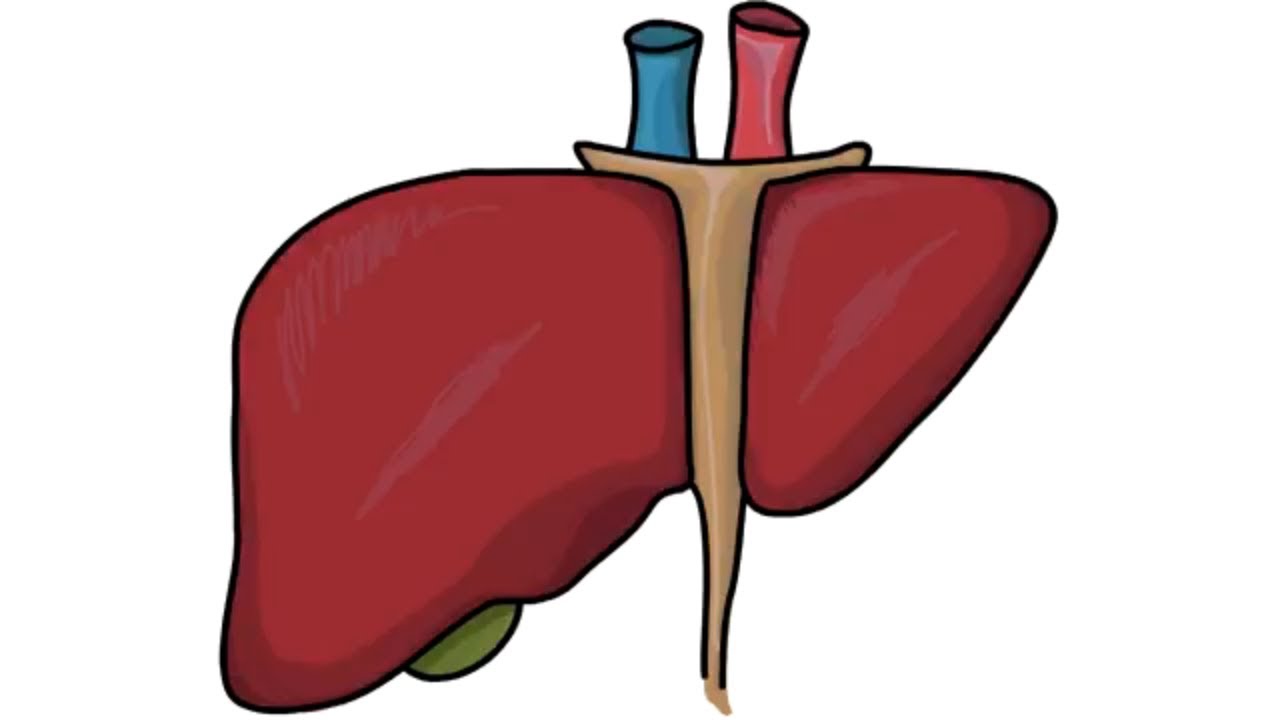

Печень рисунок